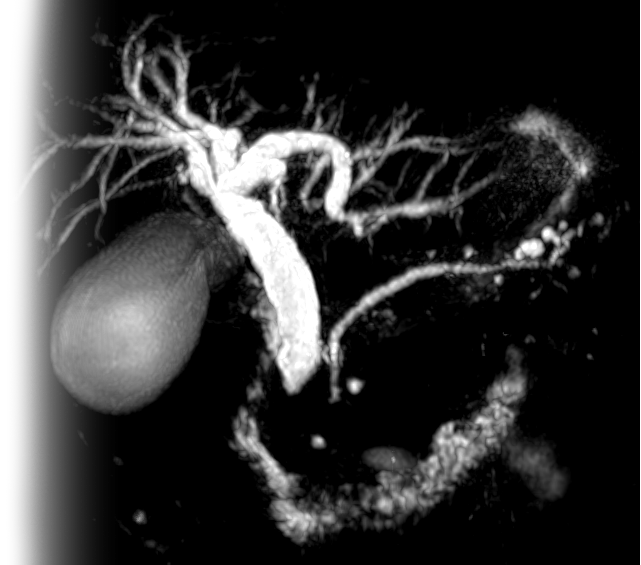

МР холангиография – важный метод исследования, который позволяет оценить состояние желчного пузыря и протоков.

Как проводится МР холангиография?

Перед укладкой в томограф необходимо снять все металлические предметы. После этого пациент ложится на стол сканера, который постепенно перемещается в аппарат. Во время сканирования следует лежать неподвижно, чтобы получаемые изображения были четкими и неискаженными.

Сканирование выполняется в течение 20 минут, что позволяет быстро получить необходимую информацию.